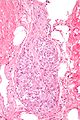

Adrenal Ganglioneuroma. H&E stain. | |

| LM | ganglion cells (large cells with large nucleus and prominent nucleolus), disordered fibrinous-like material, eosinophilic granular bodies |

Microscopic

Features:

- Ganglion cells - key feature.

- Large cells with large nucleus.

- Prominent nucleolus.

- Disordered fibrinous-like material.

- Eosinophilic granular bodies.[3]